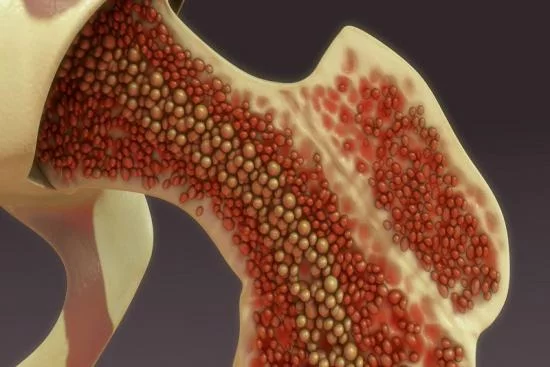

- Autografts: These are grafts taken from the patient themselves, including cortical and cancellous bone grafts.

In most cases, many doctors emphasize that it is possible to perform what is known as autografting. This type of procedure depends on choosing the source of the bone graft, which is based on various factors related to size, shape, strength, the ability to stimulate recovery and healing. Some of the prominent places where autografts can be obtained include:

- Pelvic bones.